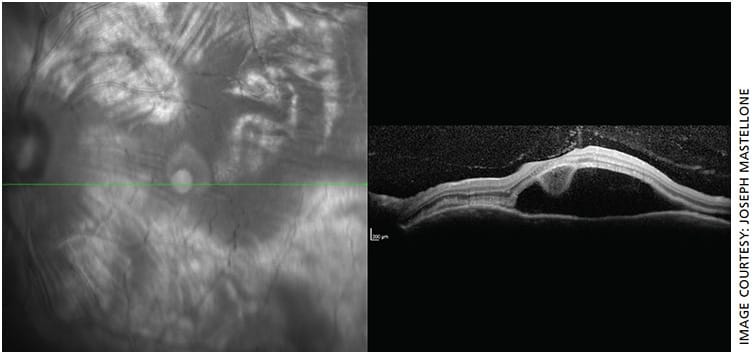

- Fundus: Cream-colored round choroidal lesions scattered throughout the macula and periphery (Dalen-Fuchs nodules) (Figure 1)

- OS macula OCT: Remarkable for large amount of subretinal fluid consistent with serous (exudative) retinal detachment (Figure 2)

Pathologically, the sympathizing eye demonstrates diffuse uveal tract (especially choroidal) thickening, sub-retinal fluid and/or exudative retinal detachment and Dalen-Fuchs nodules. Inflammatory responses are likely responsible for the uveal tract thinning, which recruits immunologic cells that accumulate underneath the retina and may cause detachment.

Dalen-Fuchs nodules are found between retinal pigment epithelium and Bruch’s membrane in approximately 33% of SO cases. They consist of epithelioid cells containing phagocytosed uveal pigment.6 Because SO closely resembles VKH, differentiating them is clinically relevant. SO spares the choriocapillaris, lacks systemic (neurological, cutaneous) symptoms and has a history of penetrating trauma.4